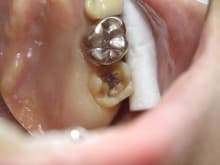

銀の詰め物がしてあった歯で

中が2次虫歯になっていました。

マイクロスコープを使用し

虫歯の取り残しが無いよう

慎重に除去しました。

治療途中です。

かなり神経に近いところまで進行しています。